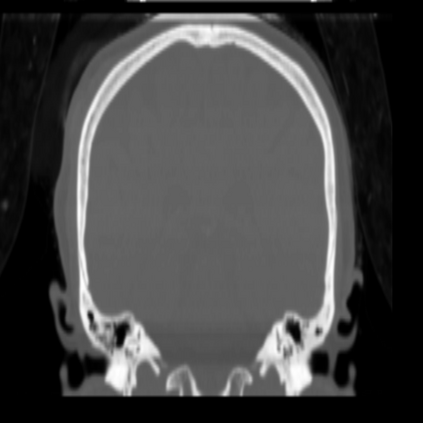

CT reconstruction provides radiologists with images for diagnosis and treatment, yet current deep learning methods are typically limited to specific anatomies and datasets, hindering generalization ability to unseen anatomies and lesions. To address this, we introduce the Multi-Organ medical image REconstruction (MORE) dataset, comprising CT scans across 9 diverse anatomies with 15 lesion types. This dataset serves two key purposes: (1) enabling robust training of deep learning models on extensive, heterogeneous data, and (2) facilitating rigorous evaluation of model generalization for CT reconstruction. We further establish a strong baseline solution that outperforms prior approaches under these challenging conditions. Our results demonstrate that: (1) a comprehensive dataset helps improve the generalization capability of models, and (2) optimization-based methods offer enhanced robustness for unseen anatomies. The MORE dataset is freely accessible under CC-BY-NC 4.0 at our project page https://more-med.github.io/